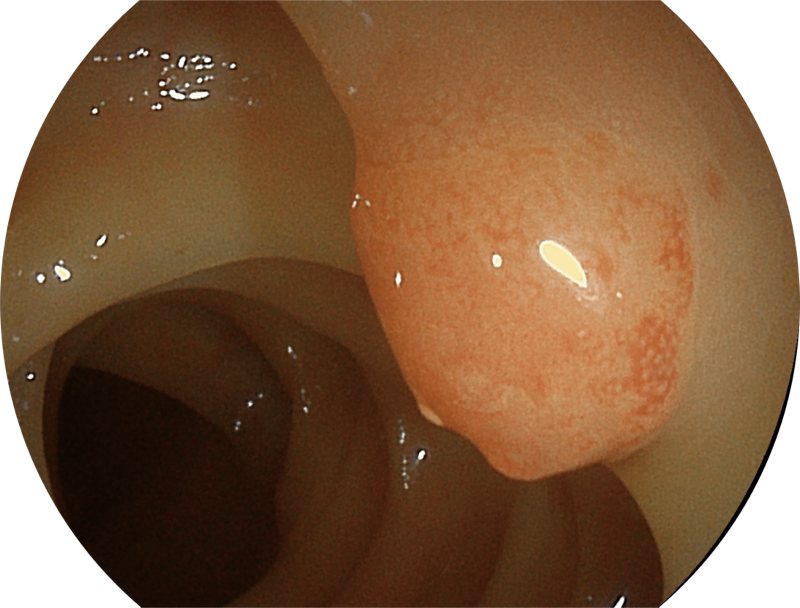

百万级像素高清传感器,1080P全高清视频信号输出,图像清晰。

白光图像